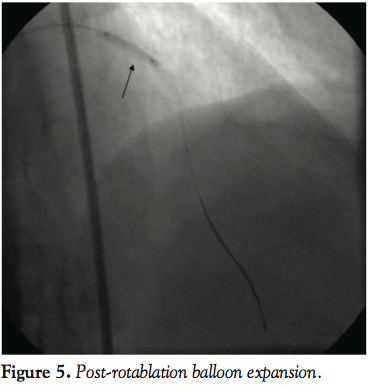

Given the limited revascularization options, we decided to proceed with careful rotational atherectomy. A Rotablator Floppy wire was tried again and did cross the lesion at this point. Gentle and extremely careful “pecking” with < 15 second runs and avoiding of > 5,000 rpm decelerations at 150,000 rpm was performed with frequent monitoring of contrast for perforation and dissection propagation (Figure 4). Four passes were performed without worsening dissection or perforation. Subsequently, noncompliant 2.25 mm balloon inflations did appear to yield the lesion and a 2.25 x 23 mm drug-eluting stent was implanted with excellent angiographic results and infarct resolution (Figure 5). Further postdilation was performed with a 2.75 mm noncompliant balloon to ensure excellent stent expansion (Figure 6). The patient was brought back for staged PCI to the right coronary artery, which demonstrated complete patency. There was no angiographic restenosis of the LAD stent at 3 months.